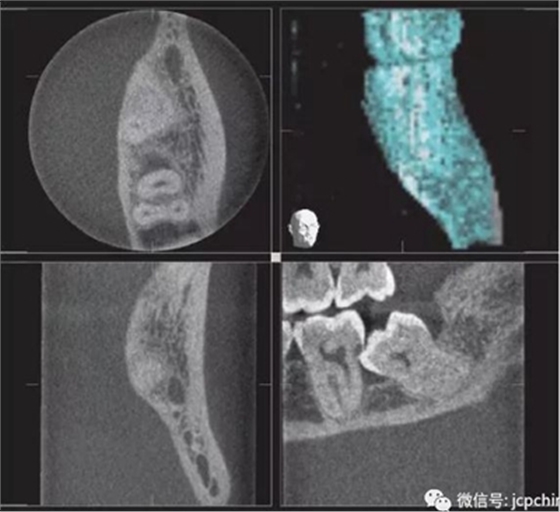

(3)部分容積效應(yīng)產(chǎn)生的偽影

如果探測器中一個(gè)高對(duì)比度物體的體積小于體素尺寸,則該對(duì)象將會(huì)有效地填充入整個(gè)體素,使其看起來比實(shí)際物體大。牙膠周邊碎片的顯影就是其中一個(gè)很好的例子,如果牙膠周邊碎片的體積小于體素大小,則圖像上會(huì)看起來比實(shí)際的大。